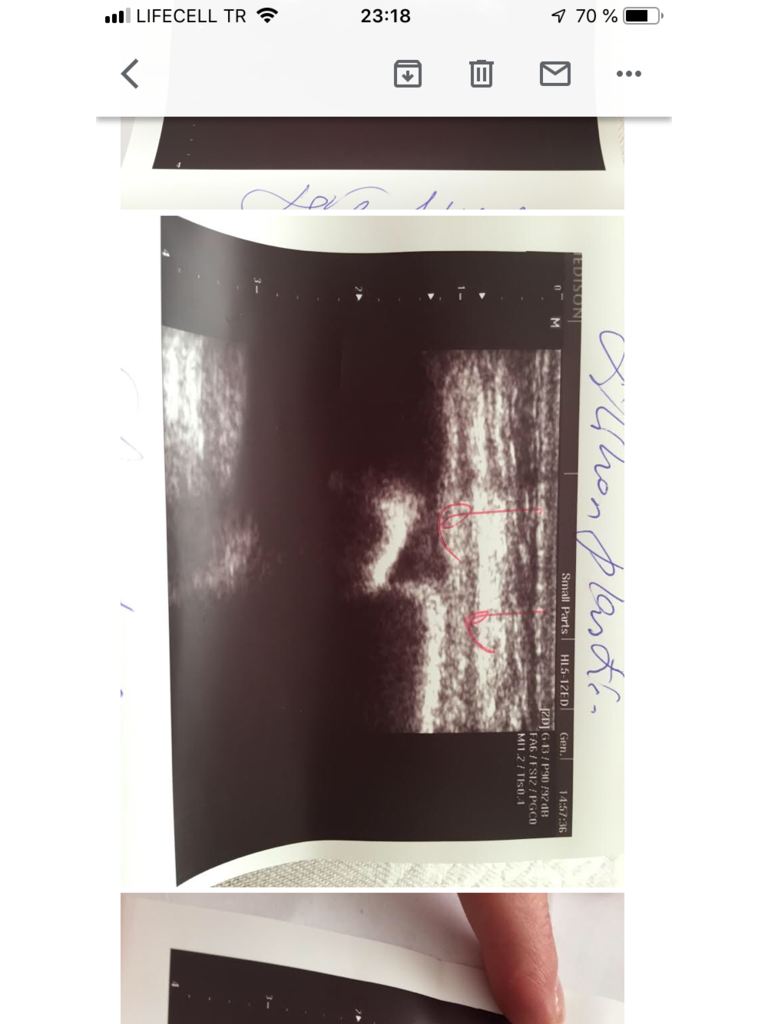

Здравствуйте. Я не помню регистрировала ли свои импланты после операции , прошло много времени, а вот сейчас столкнулась с тем , что один из имплантов лопнул и содержимое частично вышло в ткани груди ( со слов доктора УЗИ) . Возможна ли замена от производителя ? Как скоро , вообще, теперь важно имплант извлечь и заменить ? Спасибо